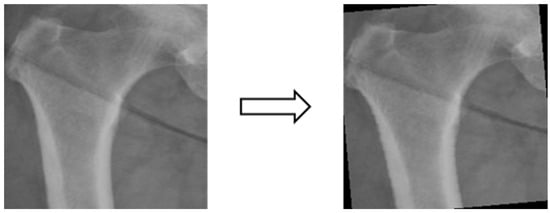

In this study, the X-ray image data were insufficient for image classification experiments. Training the model with the original dataset could lead to issues such as model underfitting and poor generalization due to the low complexity of the model and the limited image features. Therefore, the dataset consisting of X-ray images from four different body areas was augmented by applying transformations like rotation (e.g., Figure 5), shifting (e.g., Figure 6), and random scaling (e.g., Figure 7). Importantly, these augmentations were performed without altering the bone contour morphology, background, or color. The purpose of data augmentation was to aid in the training of deep learning models [30]. Additionally, data augmentation serves to address underfitting problems in classification experiments and can potentially enhance experimental accuracy if overfitting issues arise in the future [31]. Table 1 presents a comparison of data volume before and after data augmentation.

Figure 7. Image random scaling.